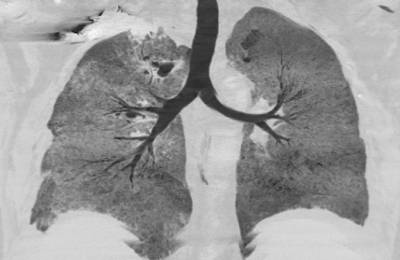

Самым распространенным методом диагностики легких является – флюорография. Но если врач подозревает, что у пациента есть спайки, то больной отправляется на рентген. По рентгеновскому снимку распознать синехию можно по мутным темным пятнам. Она выглядит, как теневое затемнение и неподвижна при вдохе и выдохе.

Плевродиафрагмальная спайка на снимке рентгена

Иногда выявляется деформация грудной клетки и диафрагмы. Чаще всего спаечный процесс отмечается в нижней части легкого. Такой вид спаек – плевродиафрагмальный, а вид спаек в верхней части – плевроапикальный.

Диагностика и лечебные мероприятия

Для обнаружения легочных заболеваний в первую очередь используется флюорография. Эту процедуру необходимо проводить ежегодно, в основном она направлена на выявление ранней стадии туберкулеза. Однако опытный рентгенолог может выявить на снимке образовавшиеся плевральные спайки, которые выглядят тенями. Причем форма их не меняется в зависимости от вдоха и выдоха.

При необходимости дополнительно назначается рентген. Как правило, спайки располагаются в нижней части легкого. При этом будет более темная картинка, а также может быть частичная деформация грудной клетки и диафрагмы.